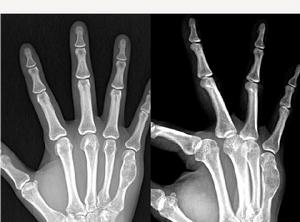

2.好發部位 骨膜軟骨瘤好發於長管狀骨特別是肱骨及股骨約占病例總數的70%。手、足部骨骼發病為25%骨膜軟骨瘤主要侵及乾骺端。典型的部位是肱、脛骨的近端及股骨的遠近端,常位於肌腱、韌帶的附著點處。